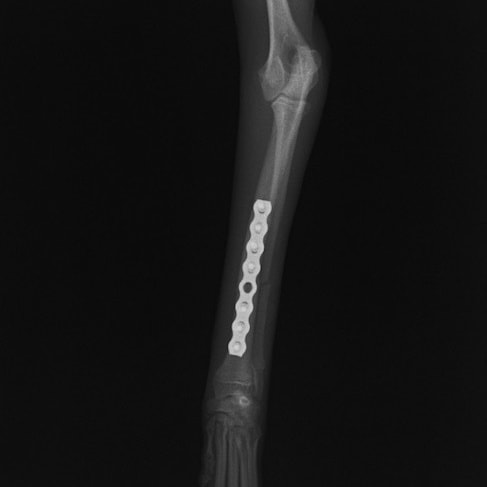

症例3:キルシュナーワイヤーのピンニングによる整復

ペルシャ猫 11ヶ月齢 雄

他院にて左大腿骨遠位の成長板骨折(salter-harrisⅠ型)が認められており、治療相談を目的として来院。当院にて、キルシュナーワイヤーを用いたピンニングにより骨折部位の整復を行いました。術後の経過は良好で、現在も経過観察中です。

術後レントゲン

Arthrex社のターゲティングデバイスを用いてピンニングの位置を調整することで、確実な固定を行っています。当院ではこの手術器具以外にも、人の手術にも使用される様々な器具を導入し、手術精度を高め、また医療メーカーと新しい器具の開発、試作にも取り組んでおります。